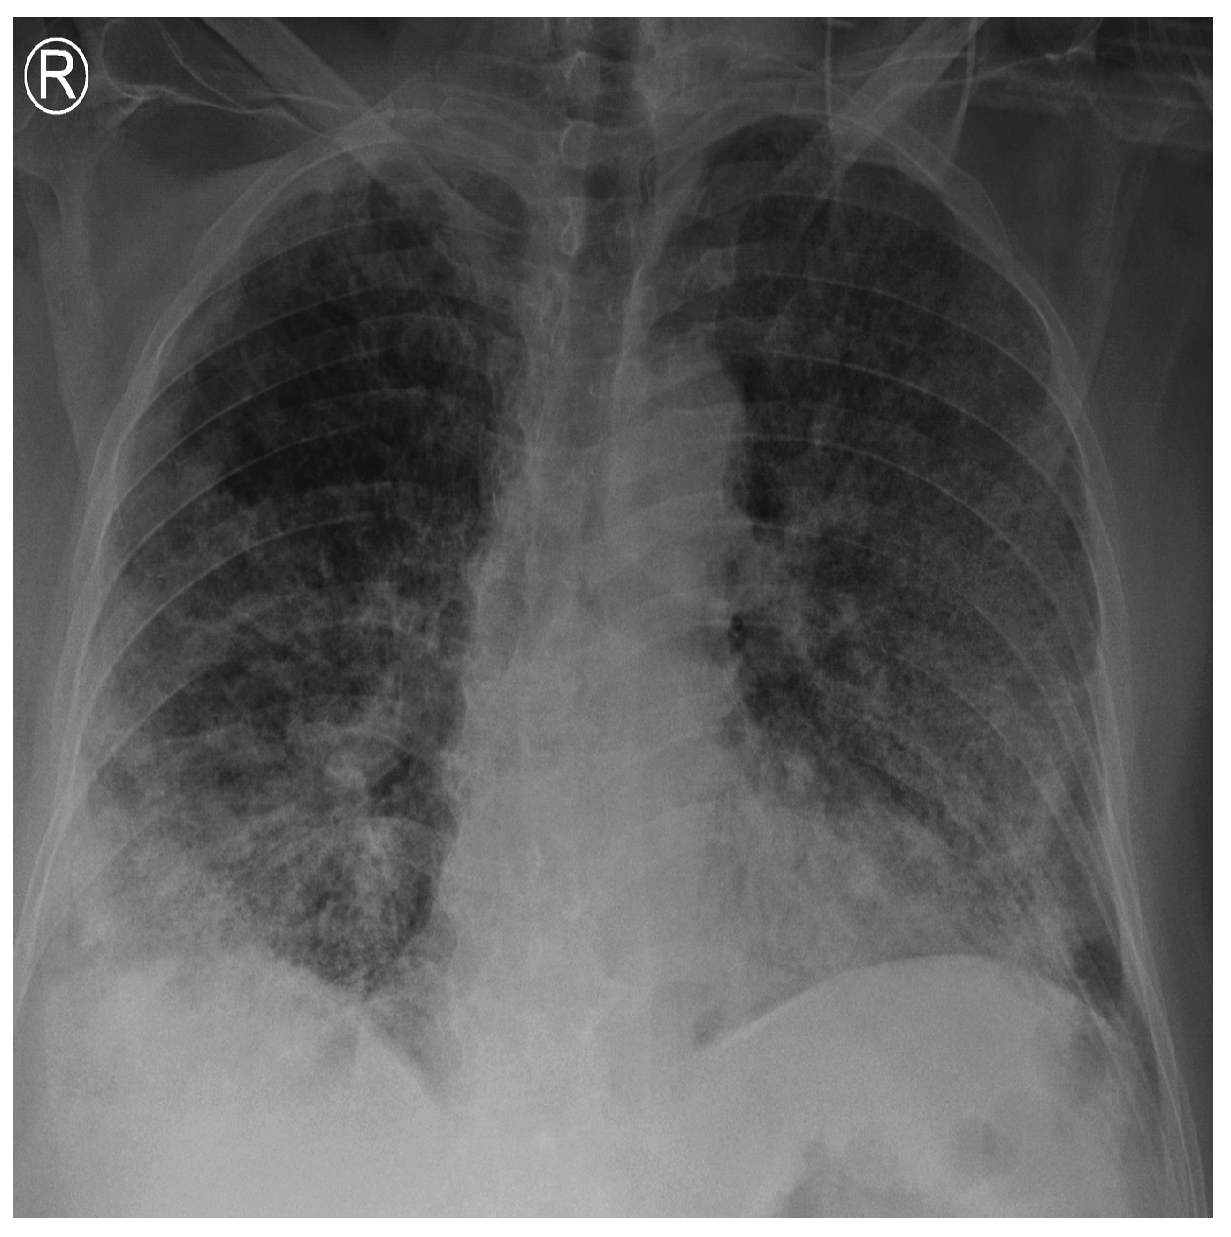

COVID-19 patients who have clinical symptoms are more likely to show abnormal CXR [9]. The main findings of recent studies suggest that these lung images display patchy or diffuse reticular–nodular opacities and consolidation, with basal, peripheral, and bilateral predominance [10]. For example, Figure 1 shows the CXR of a mild case of lung tissue involvement with right infrahilar reticular–nodular opacity. Moreover, Figure 2 shows the CXR of a moderate to severe case of lung tissue involvement. This CXR shows right lower zone lung consolidation and diffuse bilateral airspace reticular–nodular opacities, which are more prominent on peripheral parts of lower zones. Similarly, Figure 3 shows the CXR of a severe case of lung tissue involvement. This is caused by diffuse bilateral airspace reticular–nodular opacities that are more prominent on peripheral parts of the lower zones, and ground glass opacity in both lungs predominant in mid-zones and lower zones. On the other hand, Figure 4 shows an unremarkable CXR with clear lungs and acute costophrenic angles (i.e., normal).

Figure 2.

CXR of COVID-19 subject showing moderate to severe lung tissue involvement.